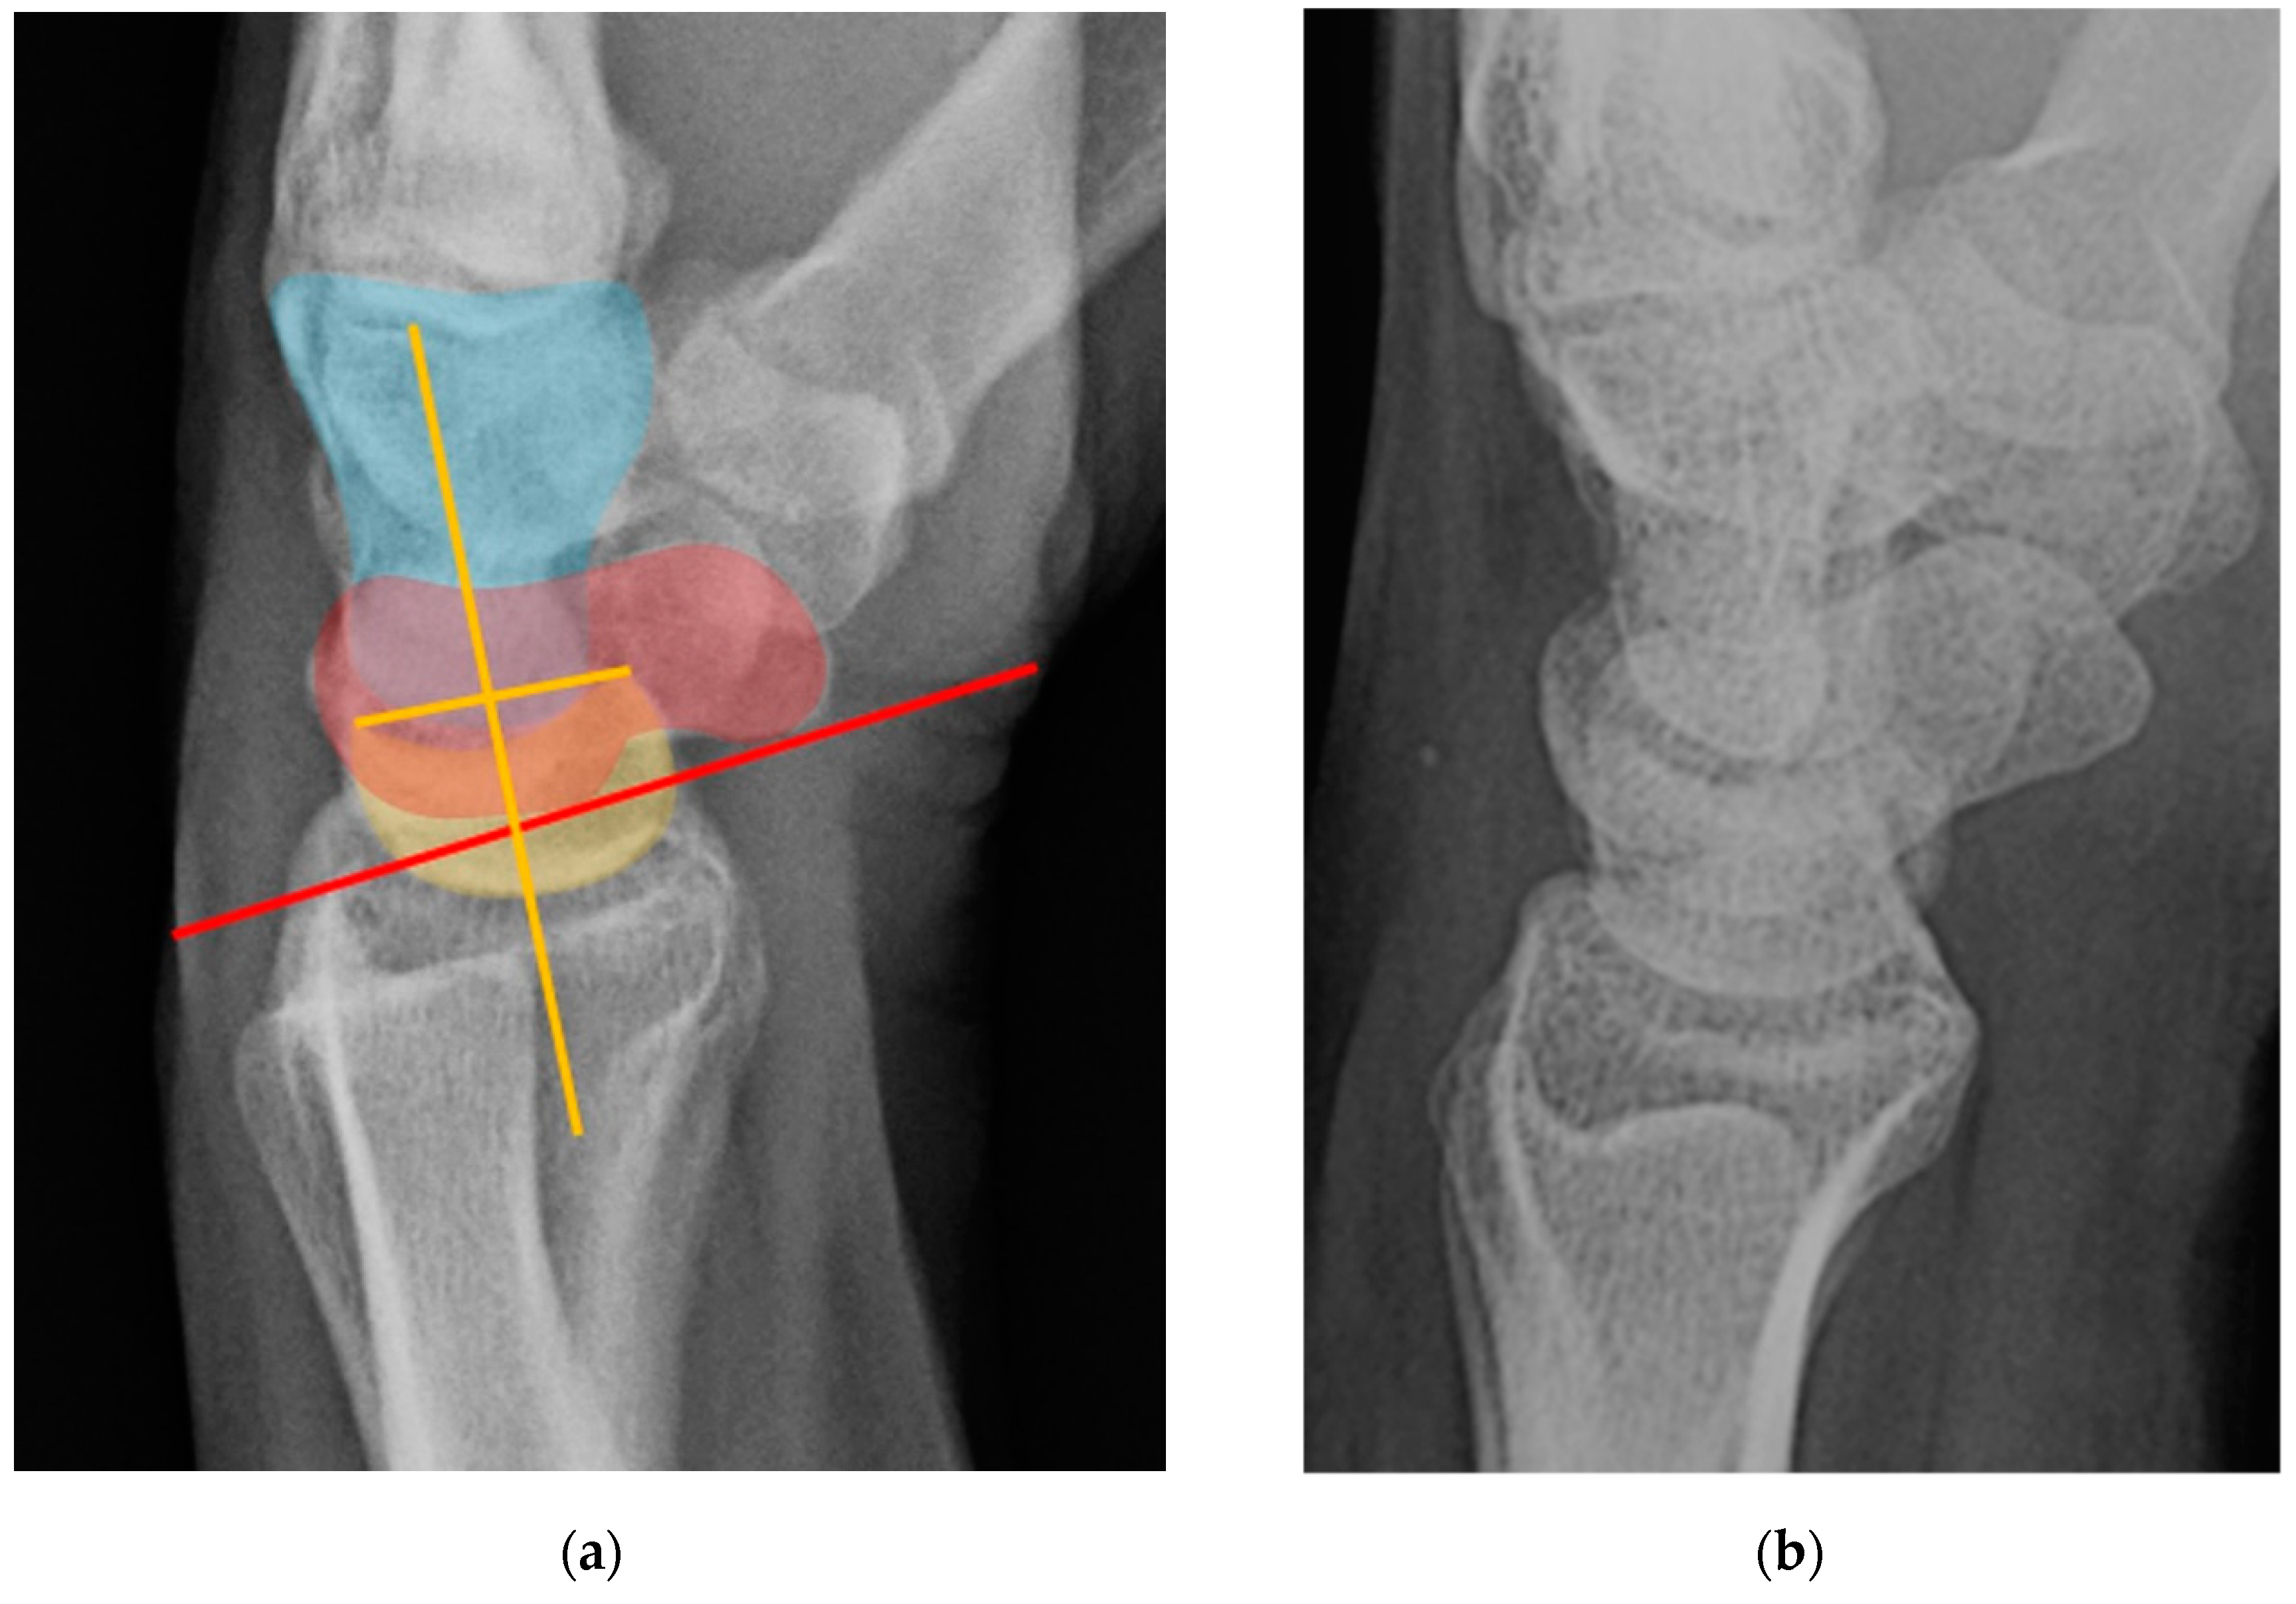

Figure 32. (a) Lateral wrist radiograph with overlay showing excessive volar rotation of the scaphoid relative to the lunate, with an increased scapholunate angle to nearly 90°. The red line is drawn along the volar surface of the scaphoid while a yellow line is drawn through the lunate axis; (b) Normal lateral wrist radiograph for comparison.

Dorsal intercalated segment instability (DISI) occurs when there is disruption of the SLL [21]. The “intercalated segment” can be considered a bone or series of bones fixed in a passive position between other active motion segments [4]. Because the proximal carpal row including the scaphoid, lunate, and triquetrum has no tendinous attachments, its motion is solely passive, dependent on the forces applied through its surrounding constraints. DISI deformity begins when the SLL loses its integrity. Because the posterior fibers of SLL are the thickest, it is the main dorsal stabilizer restricting dorsal rotation of the lunate relative to the capitate, and the volar scaphoid rotation. Rupture of the SLL disrupts the stabilizing balance and results in this malalignment pattern. On a lateral radiograph of a normal wrist, the scapholunate angle measures between 30° and 60° as the scaphoid and lunate are both held upright by the SLL. After SLL rupture, the scapholunate angle widens to greater than 60° due to excessive volar rotation of the scaphoid relative to the lunate (Figure 32) often with eventual dorsal rotation of the lunate as well [8,19]. Management of DISI and acute tears of the SLL consists of surgical repair with suture anchors and temporary K-wire fixation.